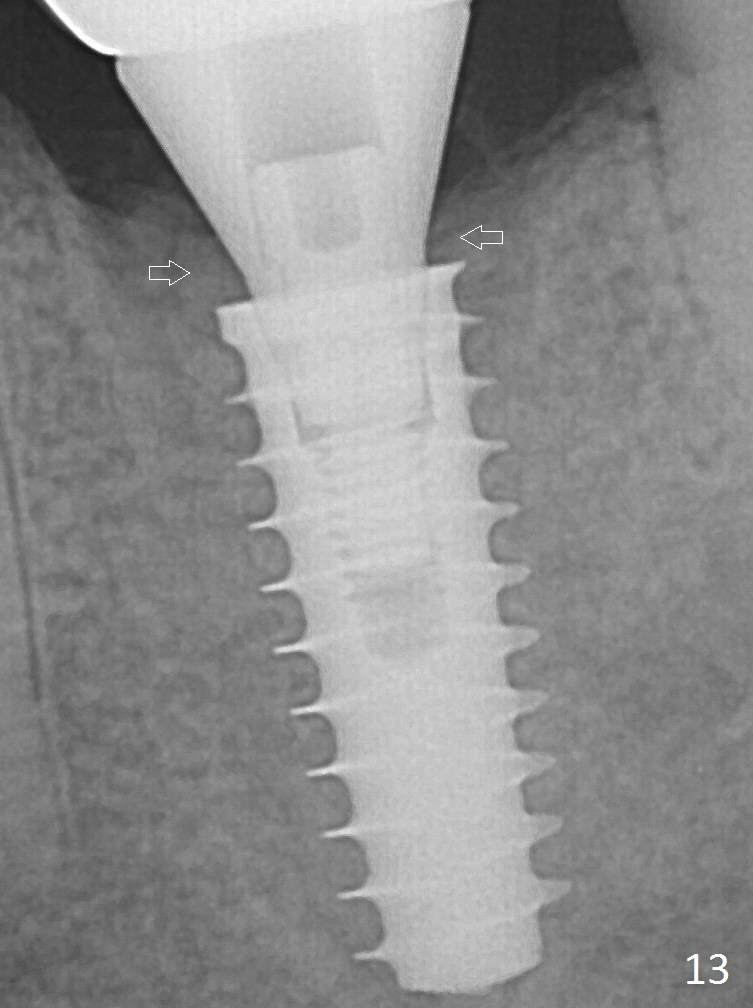

New bone has apparently covered the implant plateau 8 months postop (3 months post cementation (Fig.13 arrows)). The lower two-thirds of socket have disappeared. Bone density between threads increases 9 months post cementation (Fig.14). There is 2 mm bone superior to the implant plateau mesial and distal 1 year 9 months post cementation (Fig.15,16).